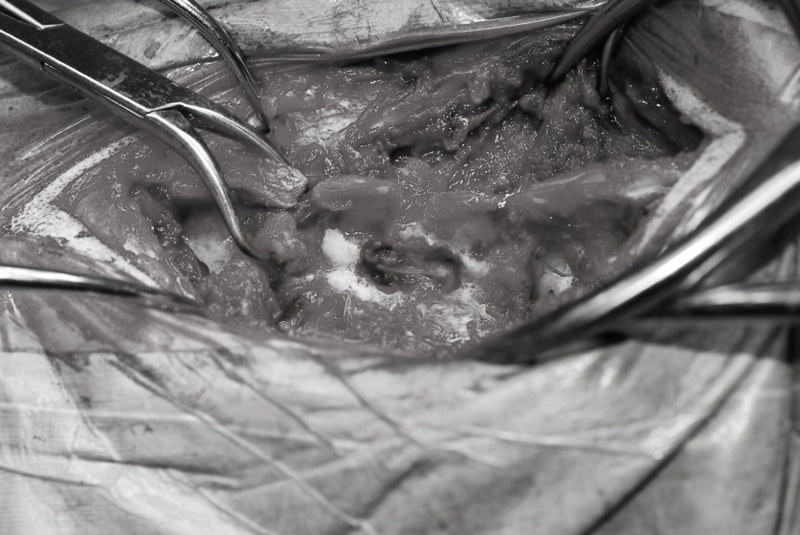

交通事故直後、胸腰部に激しい疼痛、両後肢に完全麻痺を認め、シェフシェリントン徴候を呈していました。レントゲン検査において、第11-12胸椎間の脱臼が認められました。

脊髄の減圧、脊柱管の再構築・安定化を目的に、片側椎弓切除術およびMatrixMANDIBLE Plateによる椎体固定を実施しました。

隣接椎体を架橋するようにプレートを設置しました。

術後レントゲン写真